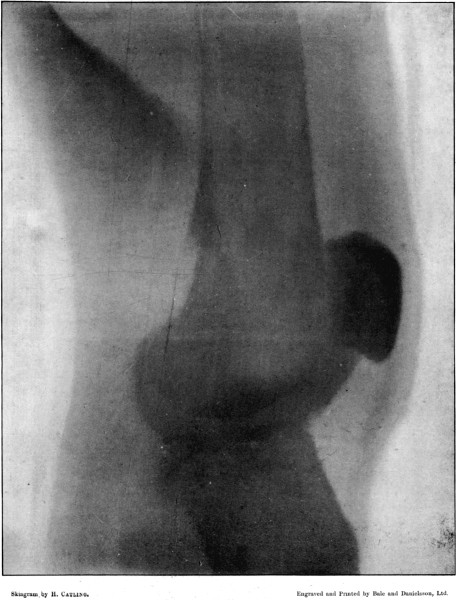

18. Fractured Patella208

19. Oblique Comminuted Fracture of the Tibia210